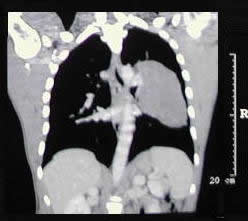

un paciente joven, con un gran tumor del mediastino anterosuperior de rápido

crecimiento, correlacionando su tamaño entre la radiografía

del tórax y los hallazgos tomográficos realizado 15 días

después, y las condiciones físicas al momento de su intervención,

con gran dificultad respiratoria.